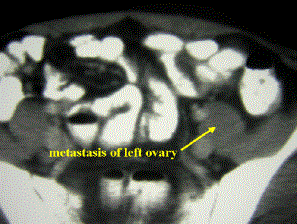

Image 1. Abdominal CT scan of the metastasis in the left ovarium.